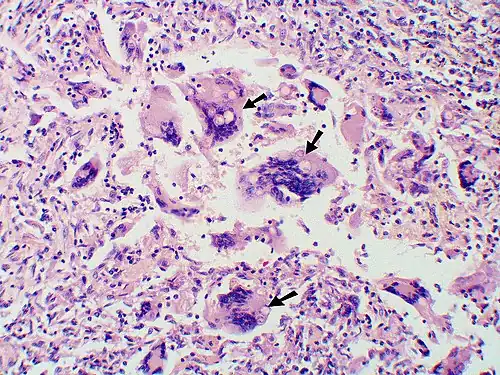

-

Granuloma with early suppuration. The fungal organisms are difficult to recognize at this low magnification. -